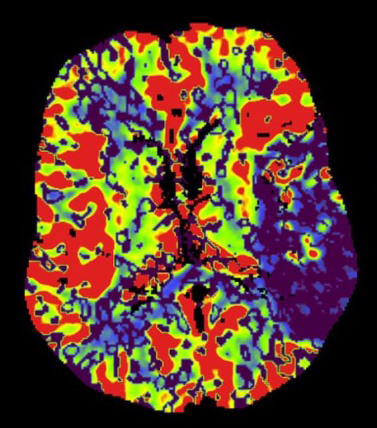

Perfuzia CT permite diferenţierea ariilor de infarctizare reală (nucleul ischemic) de ariile ischemice care sunt supuse riscului de infarctizare în lipsa terapiei trombolitice (zona de penumbră).

- în identificarea nucleului infarctului – regiuni cu CBV (volum sanguin cerebral) extrem de scăzut;

- în identificarea pacienților care prezintă zone de “țesut cu risc de infarctizare” în absența recanalizării, care pot fi recuperate cu tratament trombolitic (la debutul unui AVC acut, prezenţa unei zone de penumbră ischemică operațională reprezintă o indicaţie că terapia trombolitică poate fi benefică);